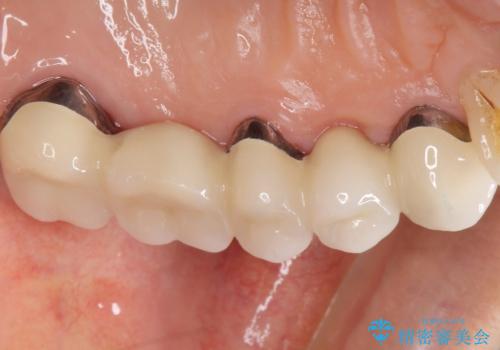

自然な仕上がりと咬み心地に喜んで下さいました。

歯茎の腫れも治り、ご満足頂けました。

クラウンの種類:メタルボンドクラウン エコノミー